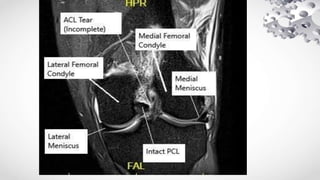

Imaging Modalities

• MRI